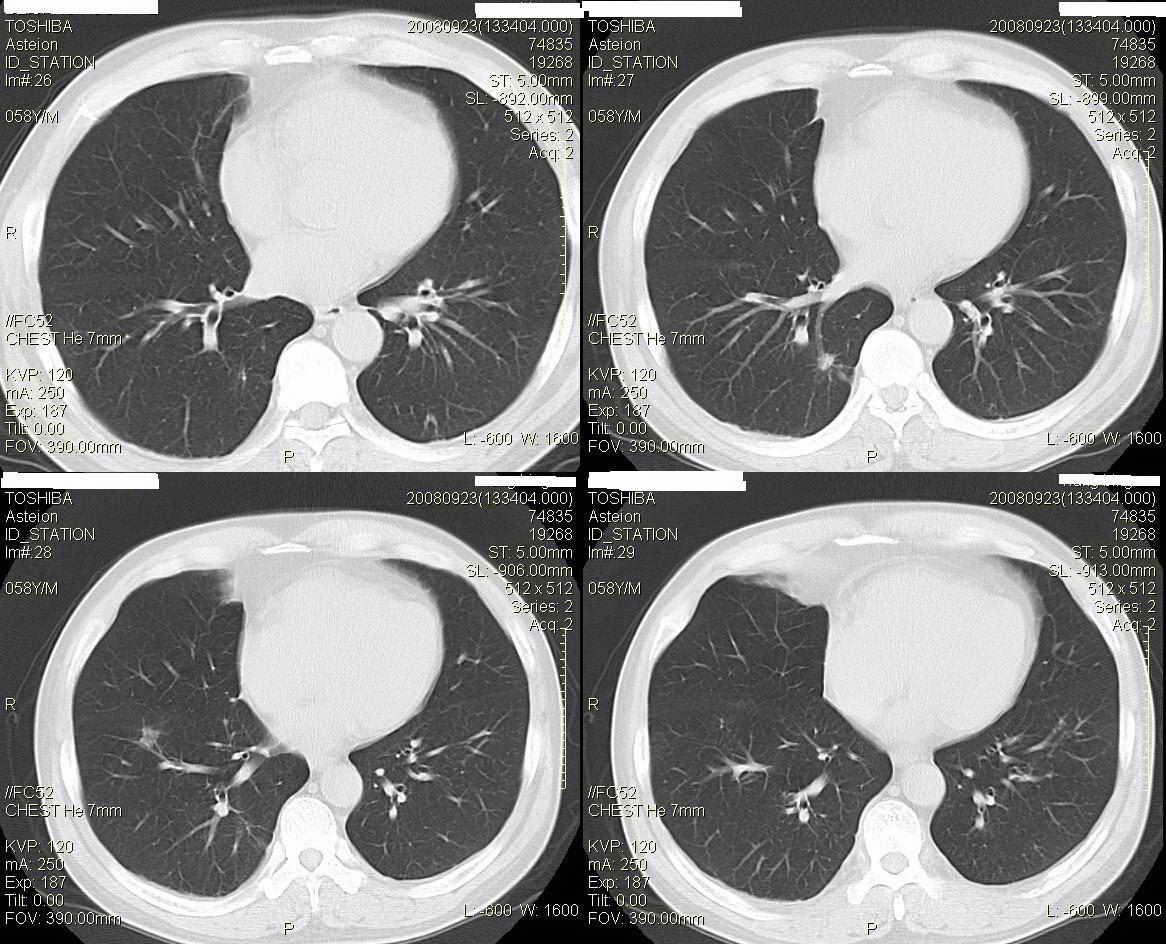

标题: CT15857:男性 58岁 咳痰带血 无发热 请各位大侠发表一下意见 [打印本页]

标题: CT15857:男性 58岁 咳痰带血 无发热 请各位大侠发表一下意见

两肺下叶肺纹理增多、增粗并呈“树芽状”改变。支气管扩张呈囊状,部分呈柱状改变。其周围可见散在的斑片样及条索样密度增高影,右肺下叶近叶间胸膜可见一形态不规则的高密度结节影,并与胸膜粘连。

考虑:支扩并发感染。

双肺多发炎性病灶,结核可能性大,建议抗炎治疗复查.右肺下叶前基底段结节灶,高度警惕肺癌可能

双肺间质性改变(间质纤维化?)伴支扩。右肺下叶有毛刺的小结节,考虑周围型肺癌可能性。